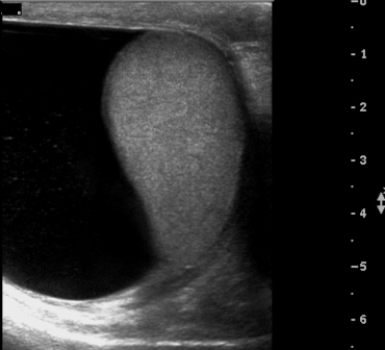

This scrotal ultrasound confirms the clinical diagnosis of:A) varicocele.

B) epididymal cyst.

C) large hydrocele.

D) testicular tumor.

large hydrocele.